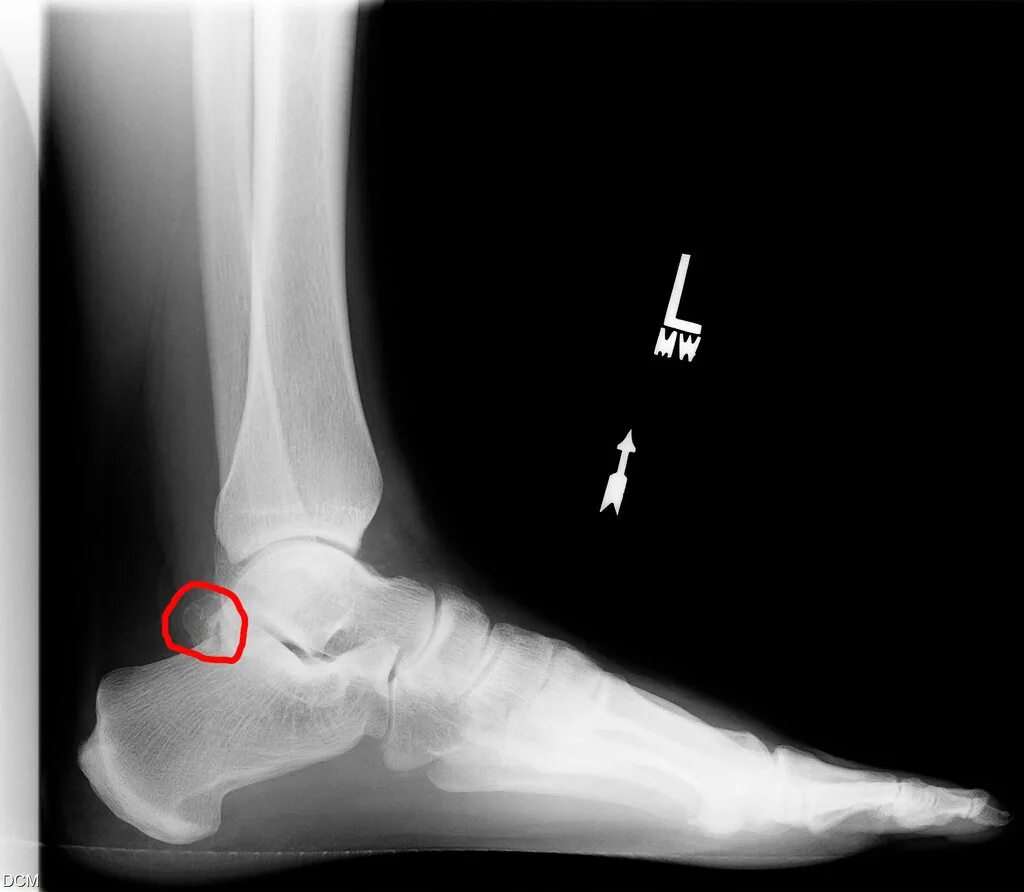

Перелом заднего